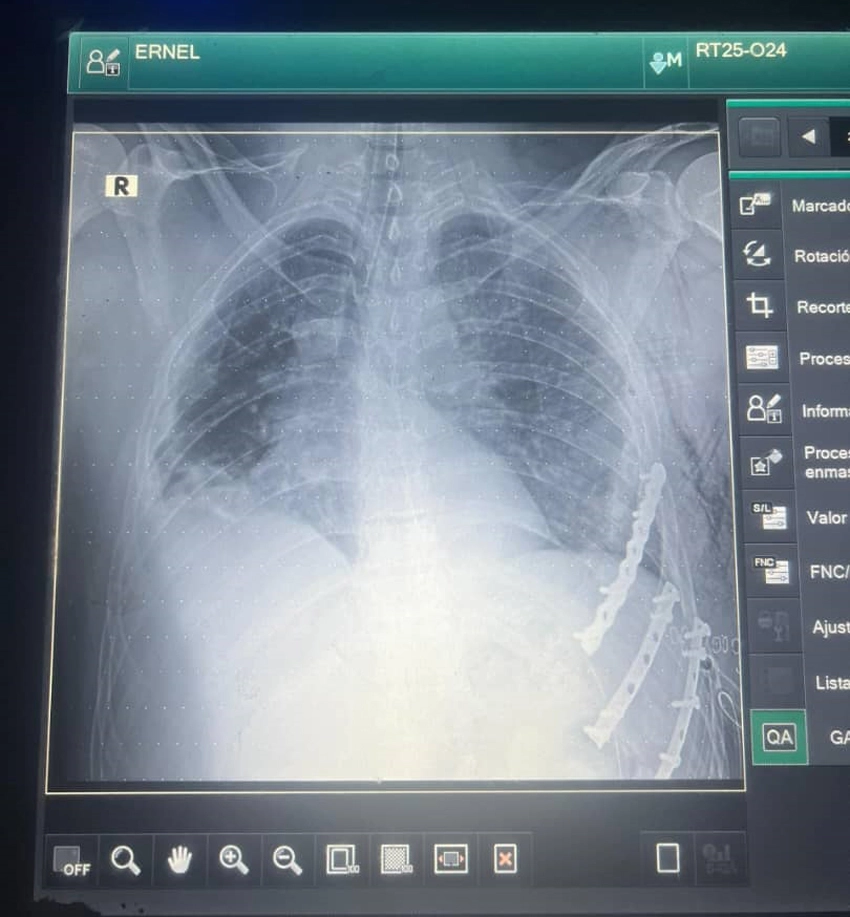

The patient’s chest was torn off by the steering Wheel. So you can imagine the magnitude of the accident. This resulted in the patient suffering blunt chest trauma, causing a flailing chest. Consisting of the loss of support of a segment of the chest wall, caused by multiple fractures of several adjacent ribs. Due to its complexity, it is considered a complex entity and constitutes a medical emergency, requiring surgical treatment.

The swift and effective response to an emergency of this nature was essential in saving the life of Ernel Sánchez González. According to the second-degree specialist in Comprehensive General Medicine (MGI), his hemodynamics were good. Additional X-ray and ultrasound examinations were performed. Which demonstrated the need for surgery.

“After opening the chest, the ribs were identified. It was necessary to open the left hemithorax because the patient had a hemothorax containing approximately 1200 ml of blood. The bleeding was controlled, and after verifying that there were no hemodynamic repercussions or risk of bleeding.

The chest wall was fine-tuned and internal fixation performed. “It was a complex surgery, lasting more than two hours. We had to work with the utmost safety and expertise so the patient could recover,” said the assistant professor.